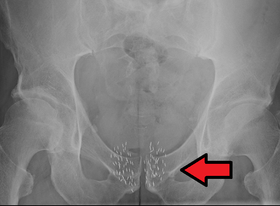

![]() Brachytherapy beads used to treat prostate cancer. Arrow marks beads. | |